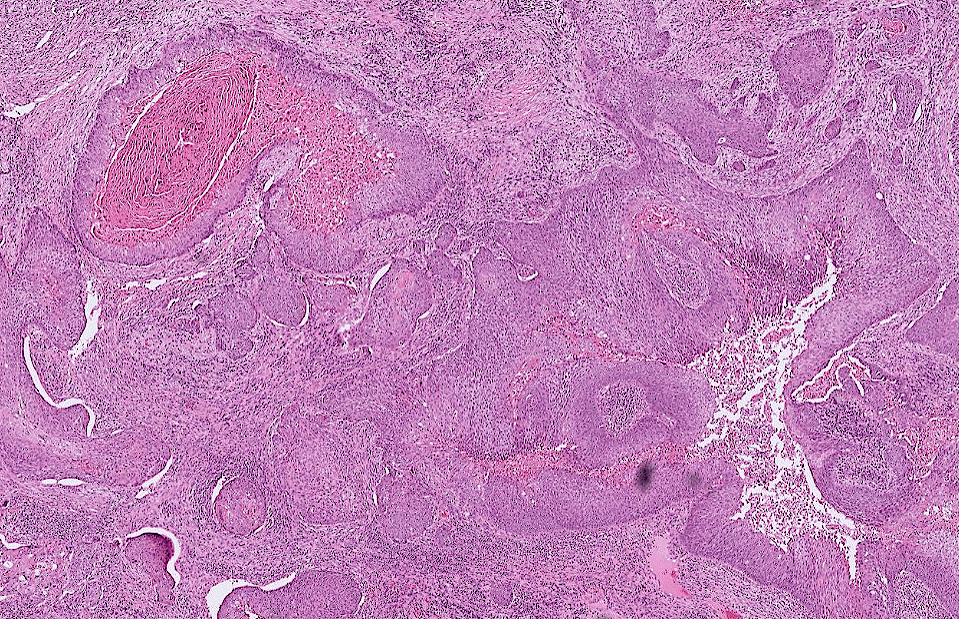

endometrial cancer